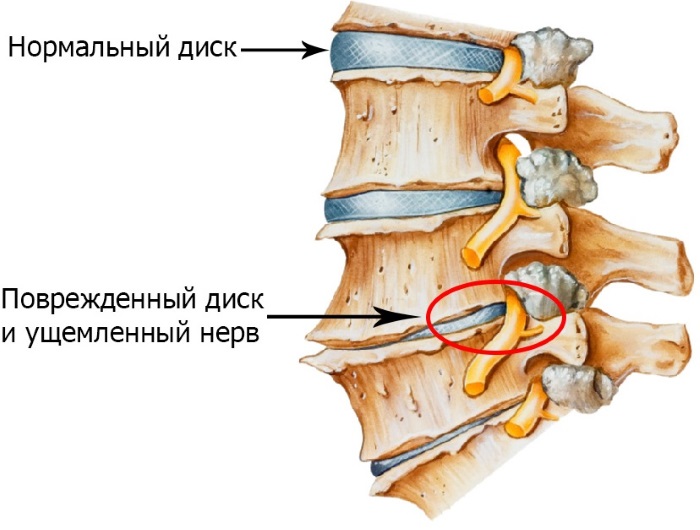

Остеохондроз

Это заболевание по праву может считаться болезнью века. В наши дни существует очень мало людей, не страдающих от него. Несмотря на то, что боль способна проявляться в самых неожиданных местах, вызывает ее поражение позвоночного столба.

В его дисках и хрящевой ткани развивается воспалительный процесс, сдавливаются сосуды и нервные окончания. При поражении грудного отдела чаще болит лопаточная область, но иногда ноют ребра, а также грудина.